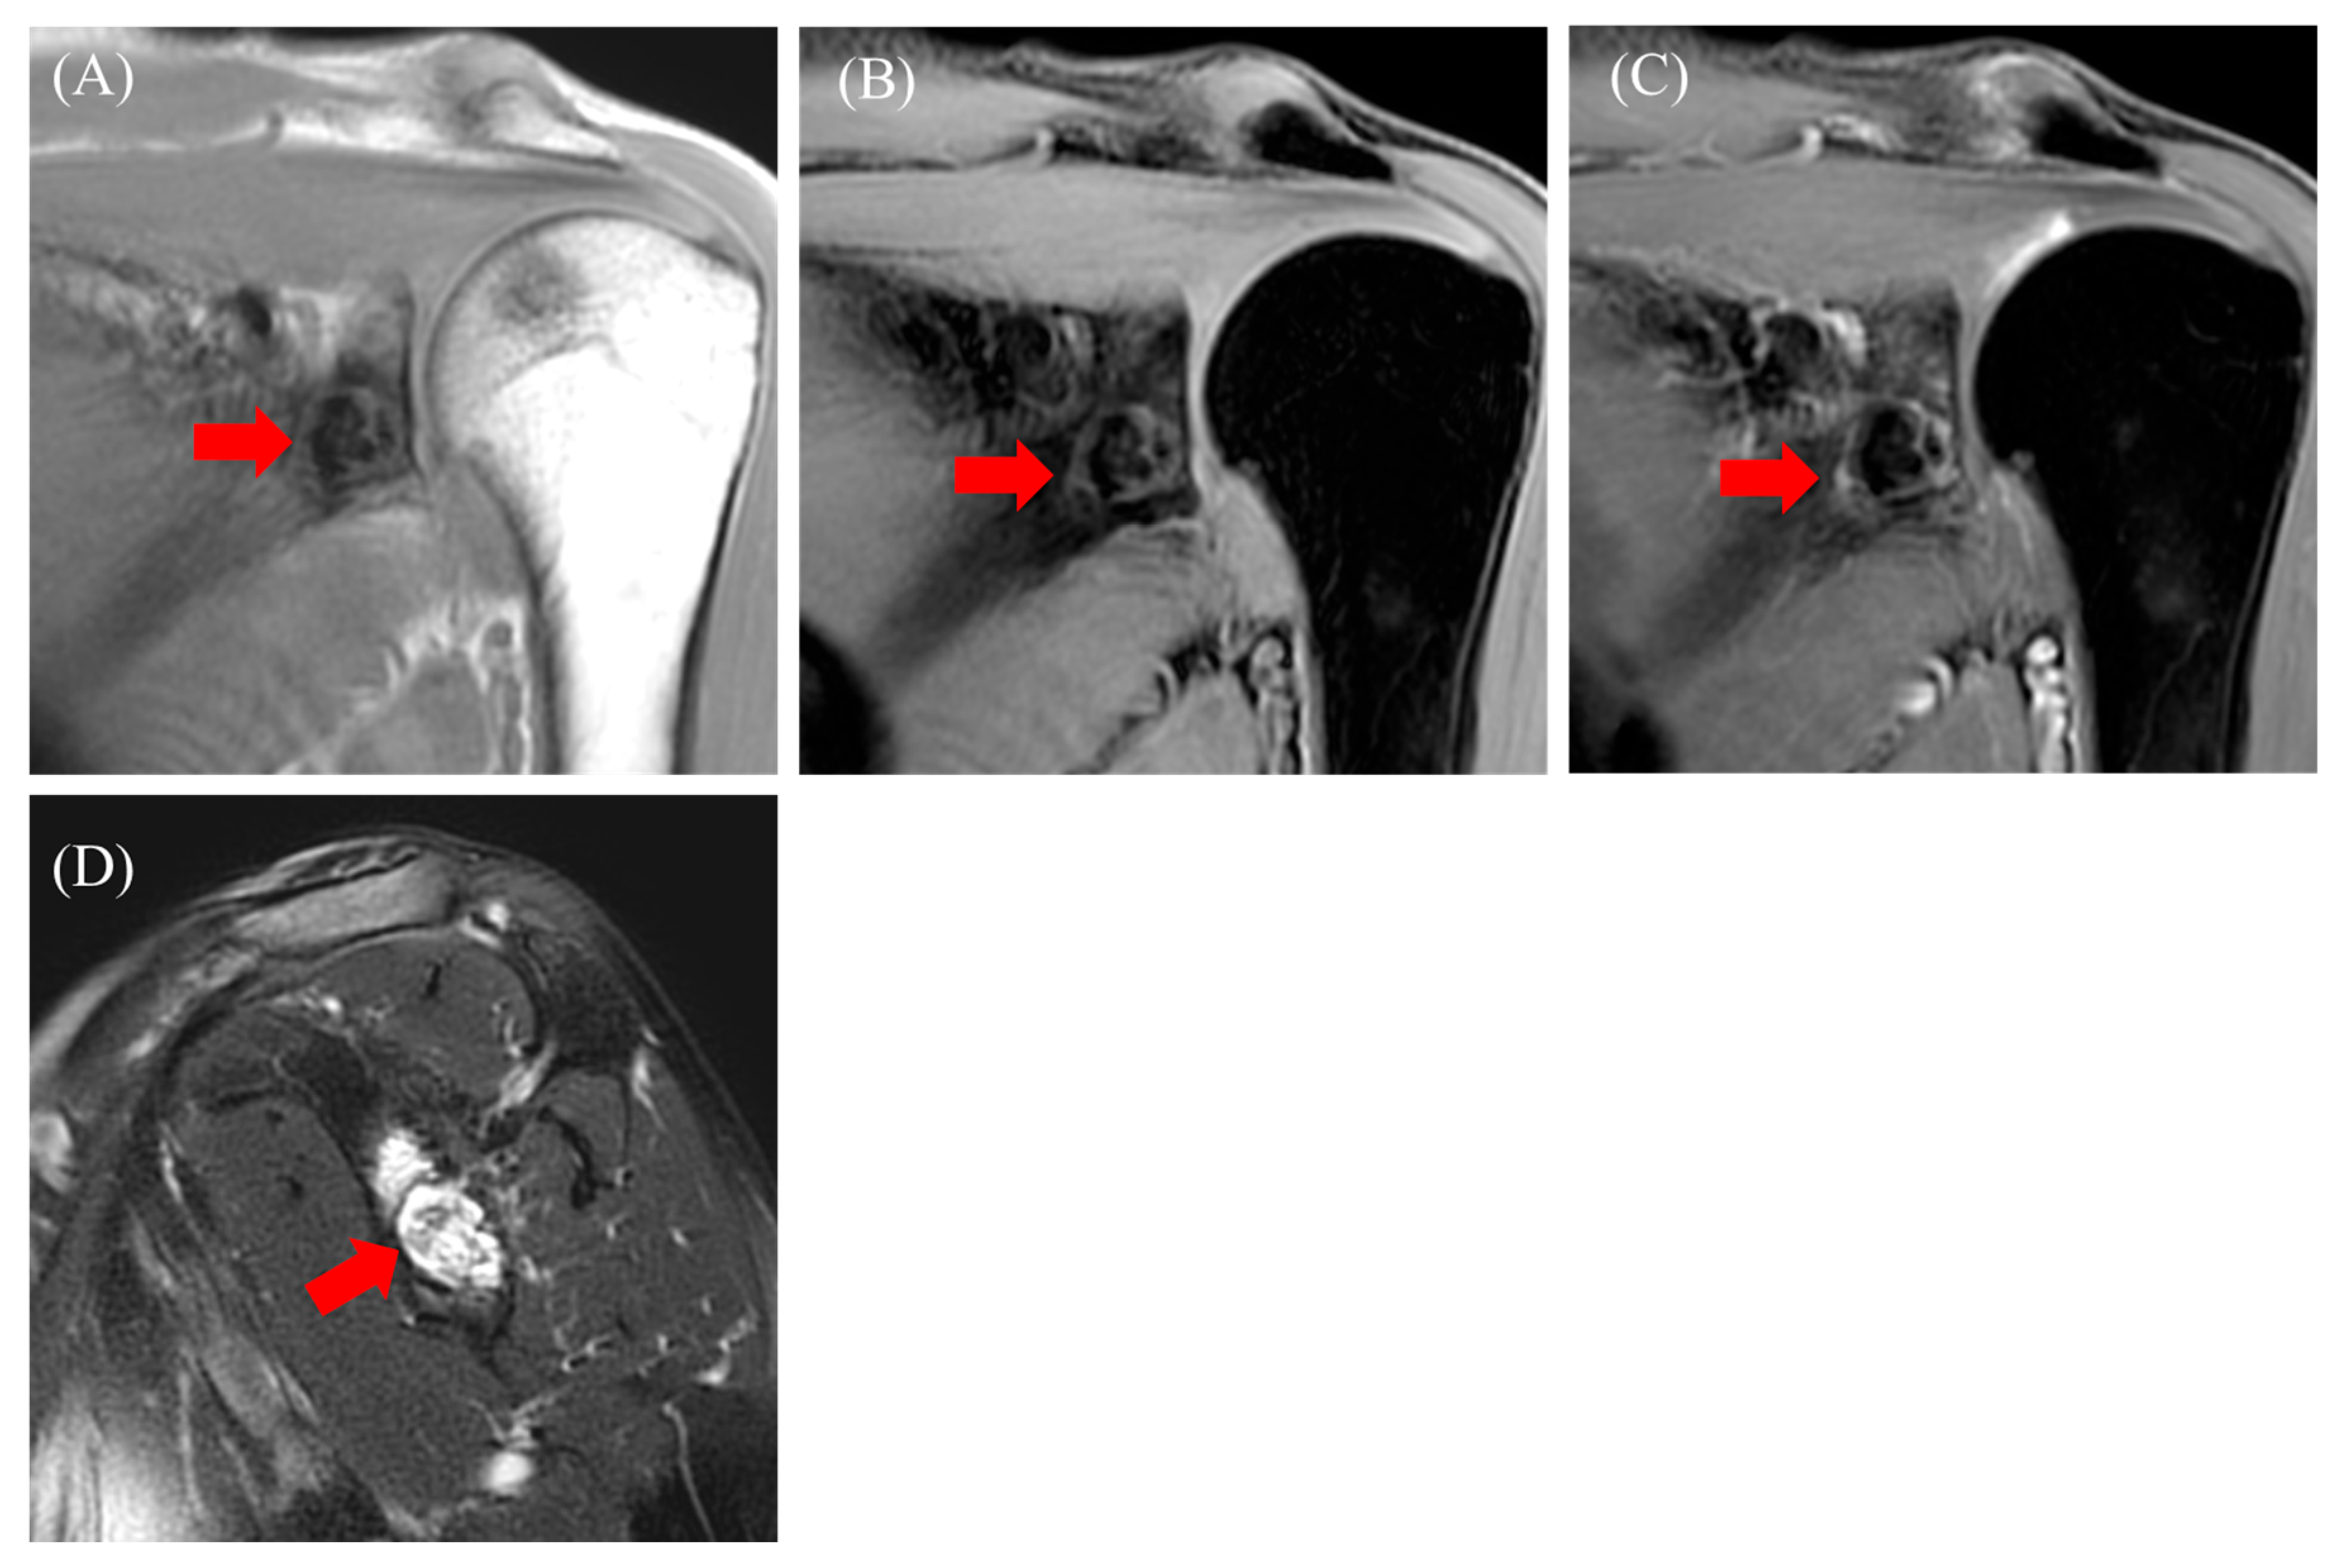

2.2. Case 2